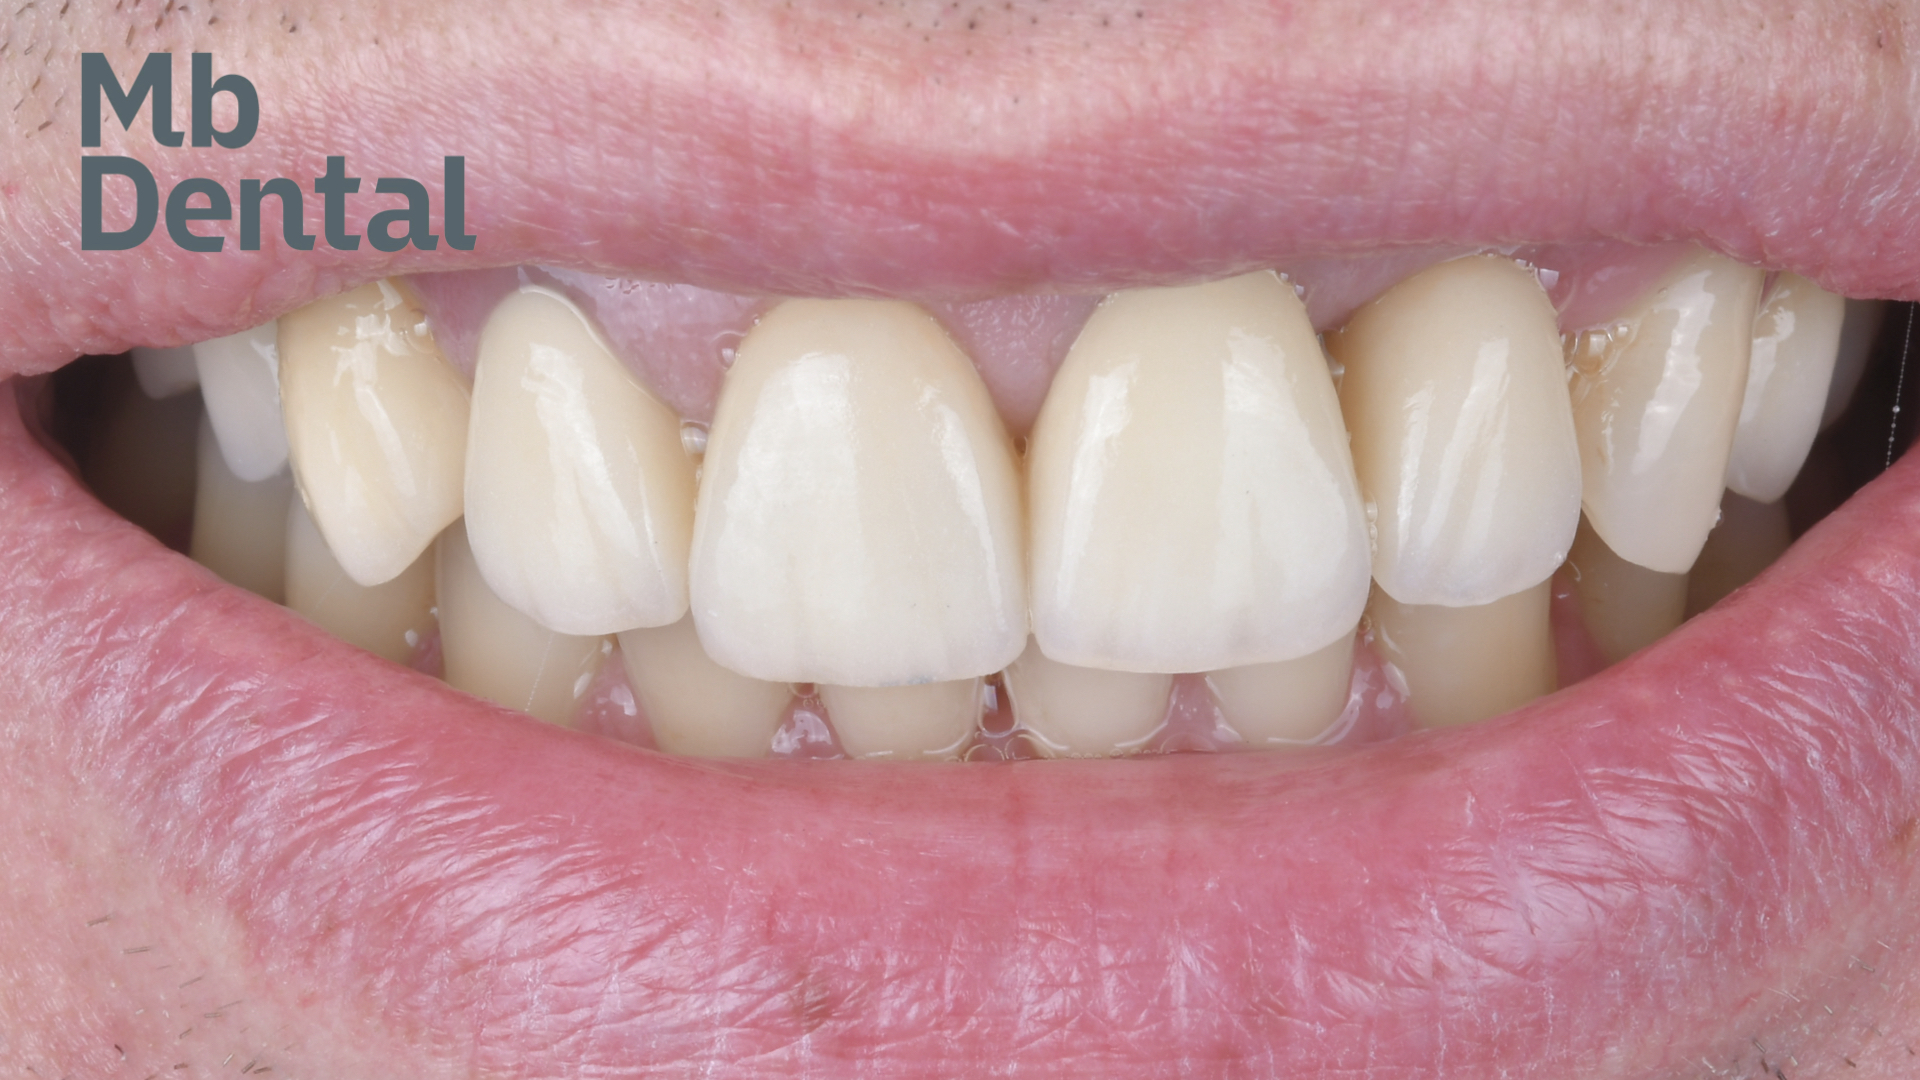

Obiectivele acestui tratament au fost restabilirea estetică dar si funcțională prin tratamente minim invazive care au inclus doua implanturi dentare, 4 coroane pe dinți naturali si o fateta ceramica.

S-a realizat inserarea unui implant imediat postextractional protezat cu o coroana provizorie. Deoarece o parte dintre dinții anteriori au fost in trecut tratați endodontic iar coroane lor au suferit modificări de culoare si tratamentul protetic final a inclus coroane din ceramica pe zirconiu pe acești dinți iar singurul incisiv care era vital a primit o fateta ceramica.